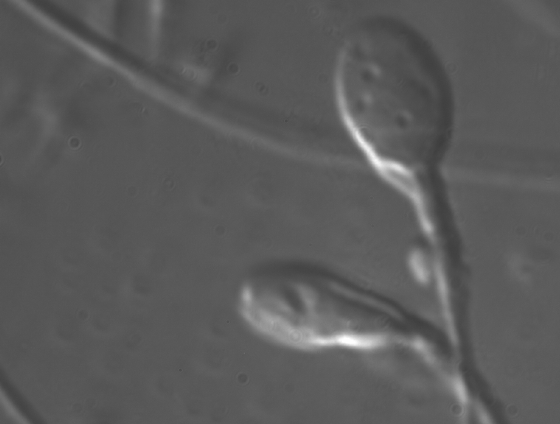

(1)精液分析:整體精子質量的評估是在進行任何受精程序之前最重要的一步。精液分析(seminogram)評估總體積、每毫升(ml)活動精子的數量和精子形態。

spermimage

圖 1:DIC技術用於精子檢測。